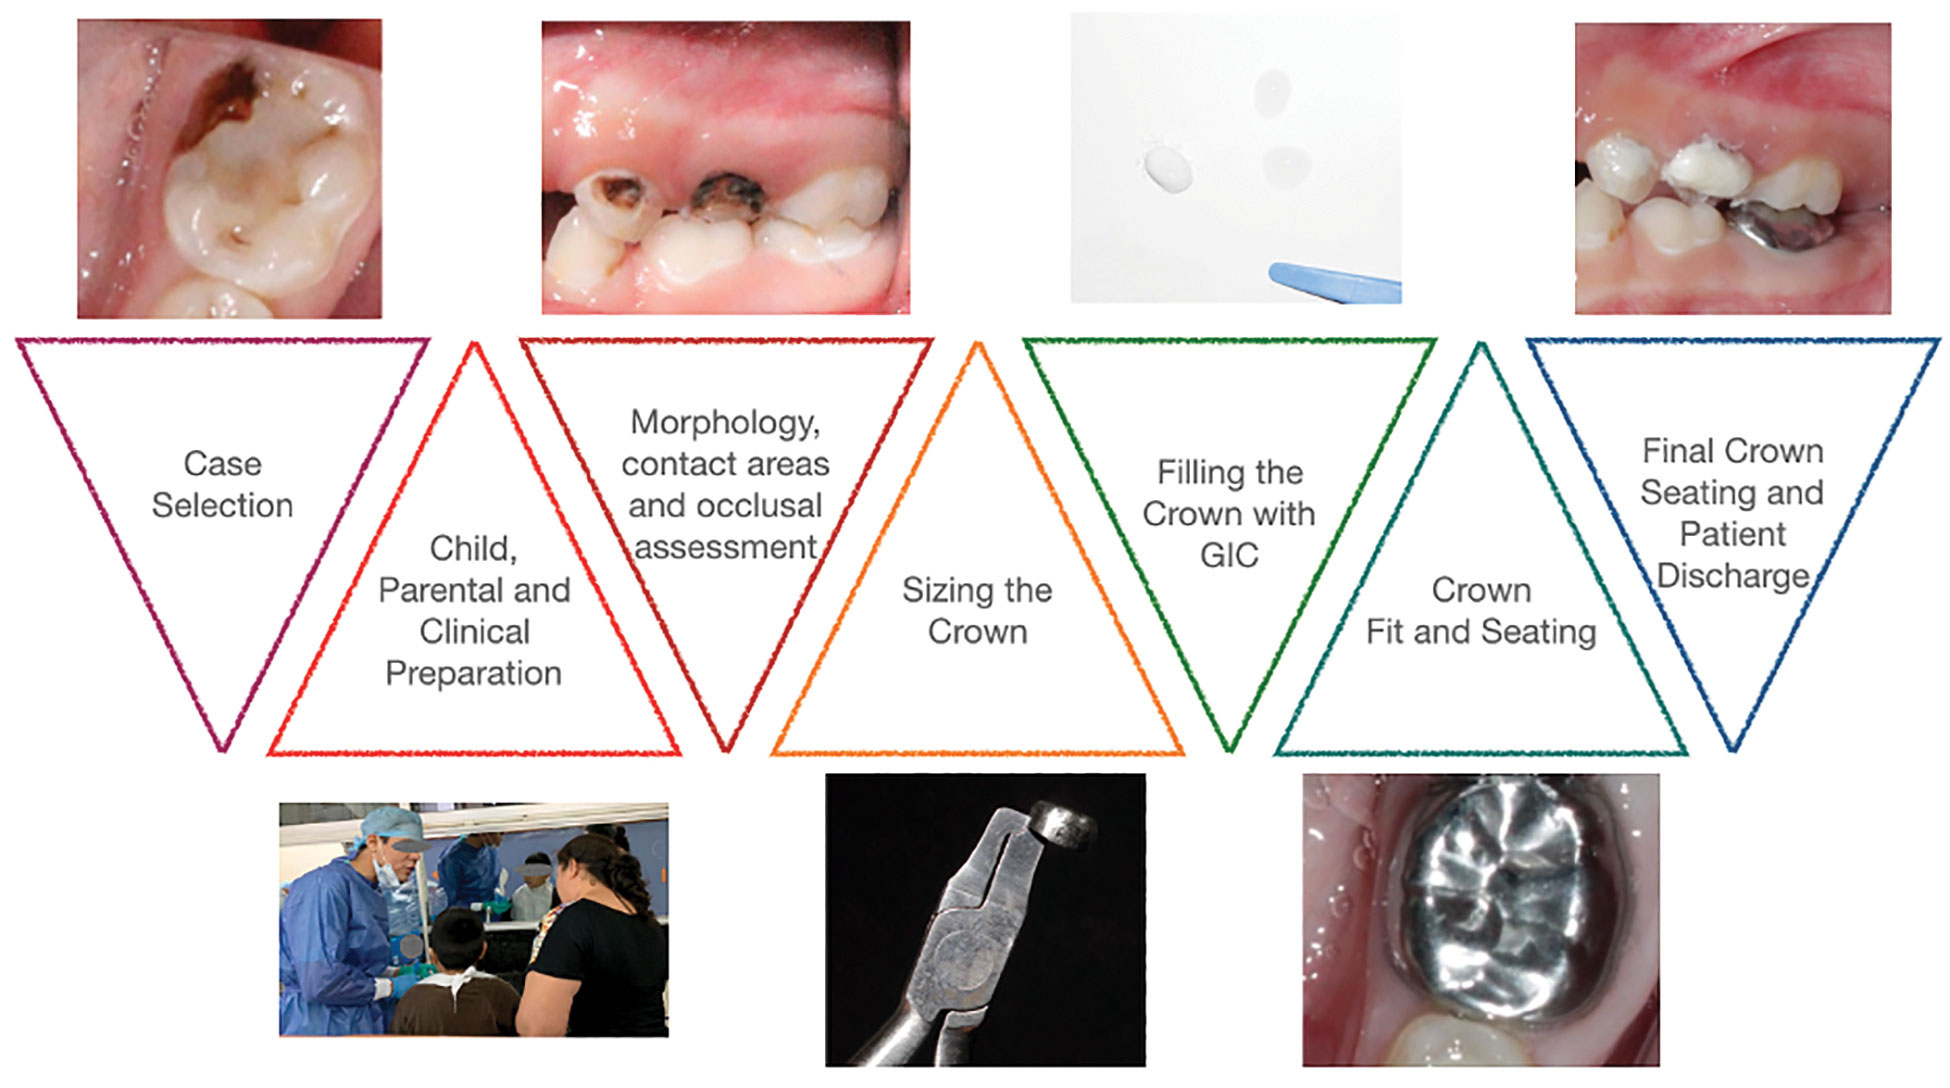

Stainless steel crowns for young permanent posterior teeth – An overview of literature and a case report

Abstract Stainless steel crowns or preformed metal crowns have become the standard for the restoration of primary teeth with extensive caries; however, they remain underutilized on permanent teeth. In this paper, we review the literature on the use of these crowns on permanent molars, and with the help of a case, discuss the indications, efficacy, … Read more